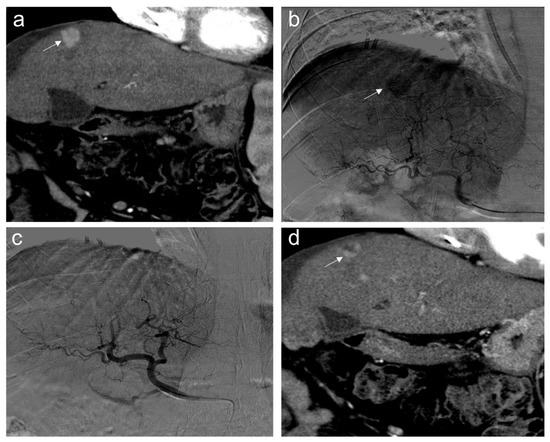

2. TACE Technique

- Eisenbrey, J.R.; Gabriel, H.; Savsani, E.; Lyshchik, A. Contrast-enhanced ultrasound (CEUS) in HCC diagnosis and assessment of tumor response to locoregional therapies. Abdom. Radiol. 2021, 46, 3579–3595. [Google Scholar] [CrossRef] [PubMed]

- Kielar, A.; Fowler, K.J.; Lewis, S.; Yaghmai, V.; Miller, F.H.; Yarmohammadi, H.; Kim, C.; Chernyak, V.; Yokoo, T.; Meyer, J.; et al. Locoregional therapies for hepatocellular carcinoma and the new LI-RADS treatment response algorithm. Abdom. Radiol. 2018, 43, 218–230. [Google Scholar] [CrossRef]